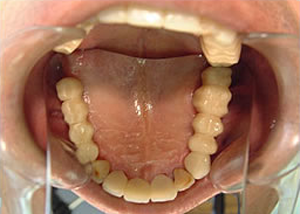

11.最終の作った歯が入った後の口腔内

12.歯が入ったところを鏡で上から写したところ

治療完了

平成18年12月18日

(治療期間:1年9ヶ月)